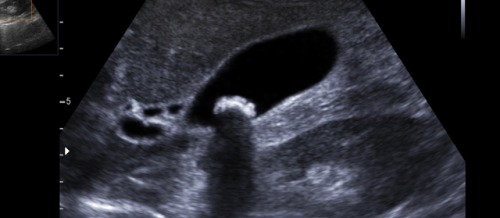

Hamiləlik dövründə ultrasəs müayinəsi, Ultrasəs müayinə, USM, Gözün ultrasəs müayinəsi

Hamiləlik dövründə ultrasəs müayinənin qiymətləndirilməsi Ultrasəs hazırda hamiləlik müayinələrinin ən mühüm hesab olunanıdır. Hamiləlikdə heç bir problem olmasa da müəy..